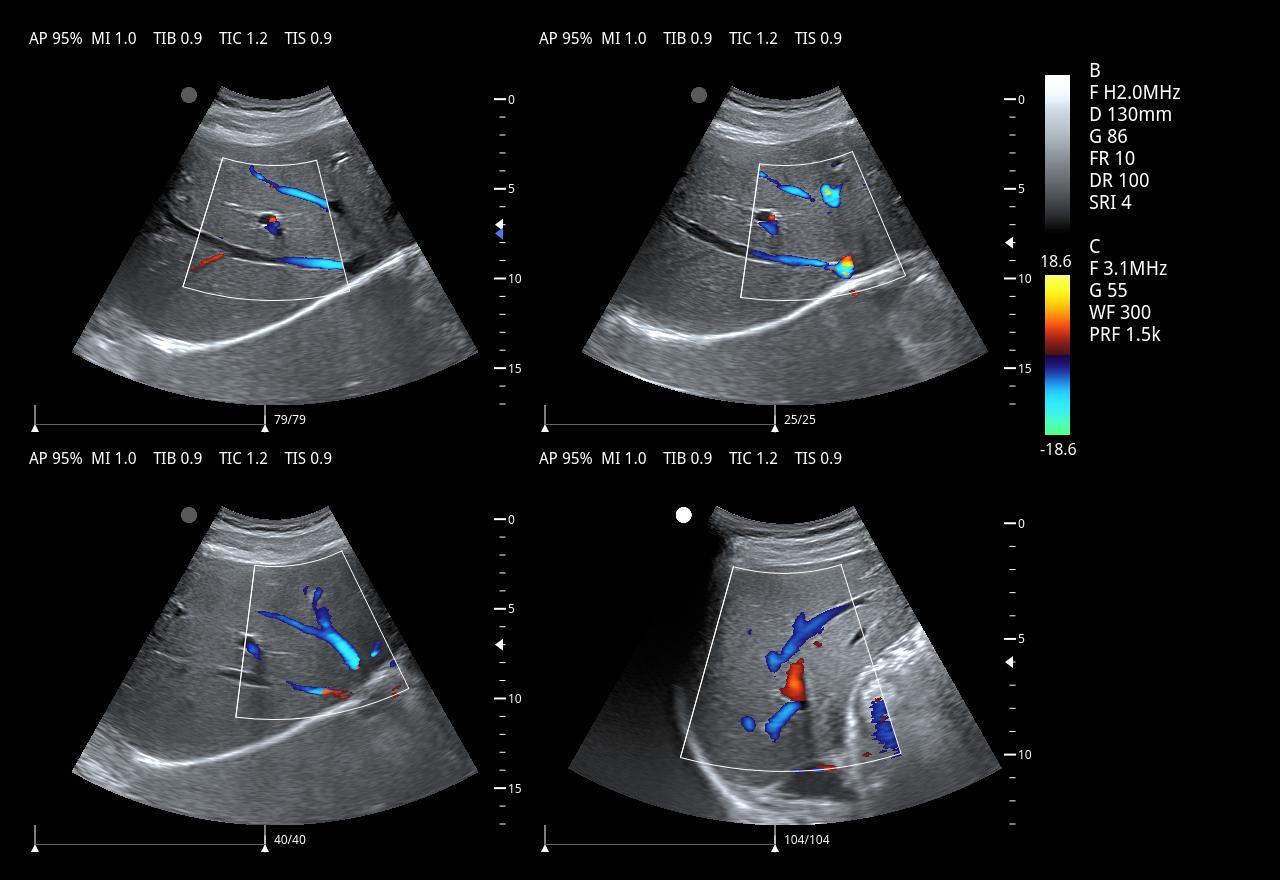

DMU28 Best-value Full Digital Color Doppler Ultrasonic Diagnostic machine

2.Imaging modes:

1)B-Mode

2)B/M-Mode

3)CM-Mode

4)CDFI – Mode

5)Anatomic M mode